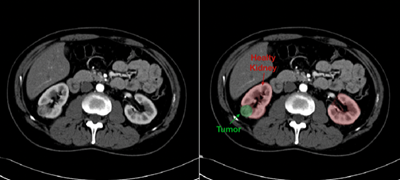

- Advanced 3D Kidney Modeling: We are the first of two centers in the U.S. to create a 3D digital model of your kidney for surgery planning and for navigation during tumor removal.

We are the first of two centers in the U.S. to create a 3D digital model of your kidney for surgery planning and for navigation during tumor removal.